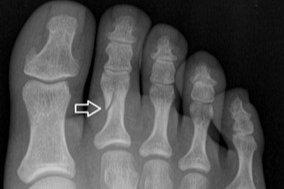

- 단순 X선 촬영이 1차

- 불분명하면 CT·MRI로 세부 골절선 확인

엄지발가락 골절 관리: 깁스 적용

엄지 깁스가 필요한 이유

- 체중 전달이 가장 큰 부위

- 중족지관절(MTP)의 엉성한 붙임 방지